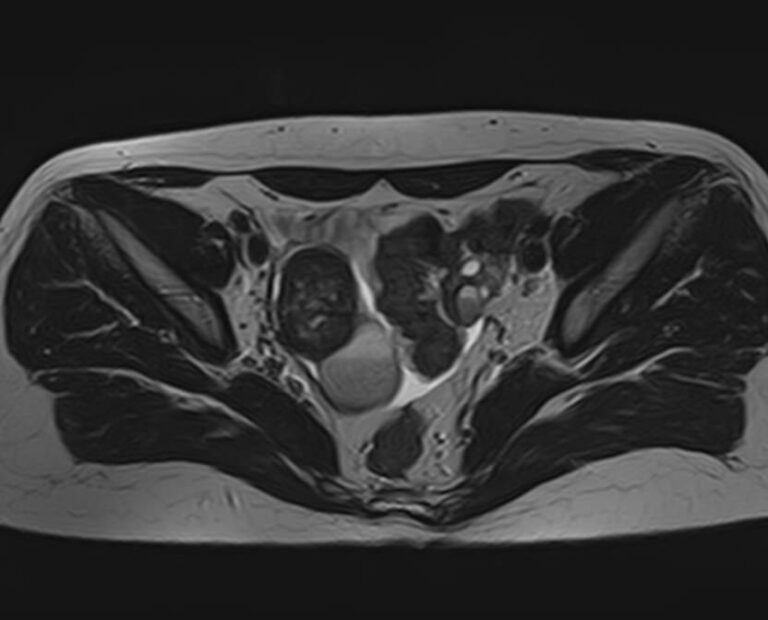

В клинике «Доступная медицина» МРТ яичников выполняется на современном томографе экспертного класса TOSHIBA VANTAGE TITAN 1,5 Тесла, который производит послойное сканирование анатомической области яичников в трех различных плоскостях с последующей цифровой обработкой полученных данных и построением трехмерных изображений исследуемой зоны.

Что показывает МРТ яичников?

На МР-исследовании могут быть обнаружены:

• пороки развития;

• снижение числа фолликулов или их отсутствие;

• функциональность имеющихся фолликулов;

• кисты;

• острое и хроническое воспаление, абсцессы;

• опухолевые процессы.

МРТ яичников: что показывает процедура

• Апоплексию яичника (разрыв придатка, сопровождающийся попаданием крови в брюшную полость и сильным болевым синдромом);

• Новообразования яичников (кисты, фибромы, рак);

• Признаки доброкачественного или злокачественного характера опухоли;

• Врожденные аномалии развития придатков;

• Признаки синдрома поликистозных яичников;

• Вовлеченность в опухолевый процесс соседних органов.